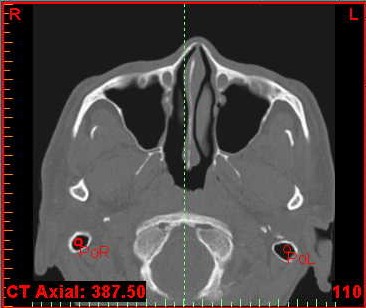

Bilgisayarlı Tomografi, MR, 3 Boyutlu Ultrasonografi gibi farklı görüntüleme tekniklerinin birleştirilmesi ile kişiye özel sert ve yumuşak doku uygulamaları ile sanal ameliyatlar, Kranio Maksillo Fasiel-CMF modulü ile pre-operatif verilerle hastanın post operatif yumuşak doku görüntülemesi, hastanın birebir ölçekli verileri ile 3 boyutlu (3B) katı modelleme ve bu modellerle tüm osteotomi ve distraksiyonun ameliyat öncesi model üzerinde tatbikatı, kişiye özel protez uygulamaları için pek çok ana bilim dalındaki hekim üç boyutlu görüntüleme yazılımı Mimics'i kullanmaktadır.

4C firmasının temsilciliğini yaptığı Mimics yazılım programı ve Z Corp. 3 boyutlu yazıcıları ile hastanın bire bir ölçekli katı modeli üzerinde tüm osteotomiler, vida, plak, distraktör uygulaması, yörüngelerininin doğrulanması, kişiye özel protez tasarımı mümkündür...